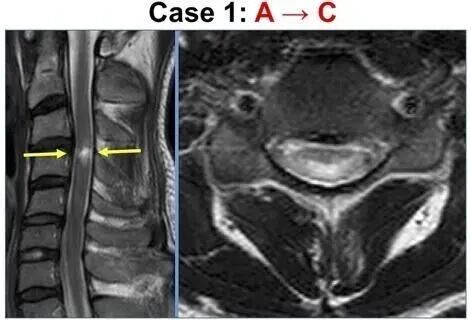

一名34岁男性因从高处坠落,结果判定为C5,脊髓损伤(AIS A)间充质干细胞回输后8天肛门出现感觉,评分升为B,回输两周出现下肢自愿运动,评分为C。在最终检查中(间充质干细胞回输后184天),患者可以进食,并用带有座位的助行器装置开轮椅约100 m。